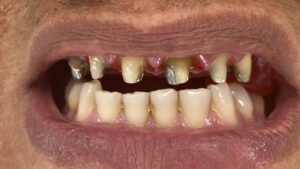

Creí, durante muchos años, que nunca iba a volver a verme sonreir en el espejo. Perdí todos mis dientes. Cuando tomaban fotos evitaba reirme. Perdí la seguridad para hablar en público, incluso comer fuera de casa mi casa me daba vergüenza.

Decidí recuperar mi sonrisa y fui a la clínica dental donde me atendió la Dra. Laura Zárate. Me explico paso a paso como sería el procedimiento. Resolvió todas mis dudas y me dio la confianza para iniciar el tratamiento.